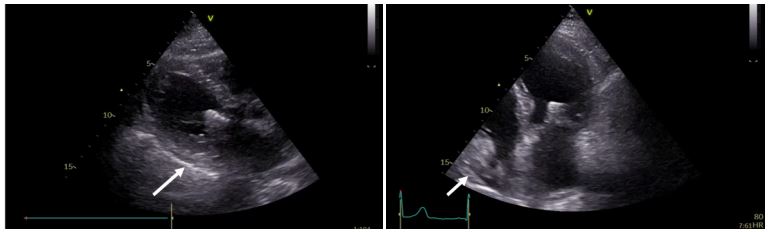

Bedside echocardiography was performed and showed mild circumferential pericardial effusion, without evidence of hemodynamic compromise (Figure 2). A chest X-ray revealed a small left pleural effusion (Figure 3). Echocardiographic studies from day 1 and 2 after the initial operation were reviewed and did not show any pericardial effusion. Thus, the patient had a newly developed pericardial effusion on day 3. Laboratory exams showed elevated white blood cells and c-reactive protein, with negative values of procalcitonin and negative blood cultures on multiple samples. Mechanical and infectious causes of pericardial effusion had been excluded. Post-cardiac injury syndrome was considered as a possible working diagnosis.

Figure 2: Focus bedside echocardiography showing mild circumferential pericardial effusion (white arrows).